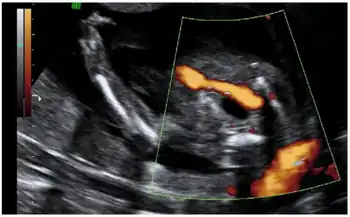

It can be detected in the first trimester of pregnancy with the use of 2D ultrasound. The sonographer is able to identify a 2 vessel cord in an image with the bladder and color Doppler, which will show only one artery going around one side of the bladder. In a normal fetus, there would be 2 arteries (one on each side of the bladder).[5] Echocardiograms of the fetus may be advised to ensure the heart is functioning properly. Genetic counseling may be useful, too, especially when weighing the pros and cons of more invasive procedures such as chorionic villus sampling and amniocentesis. These invasive procedures are usually performed when there is a suspected chromosomal abnormality or genetic defect and will confirm a diagnosis.